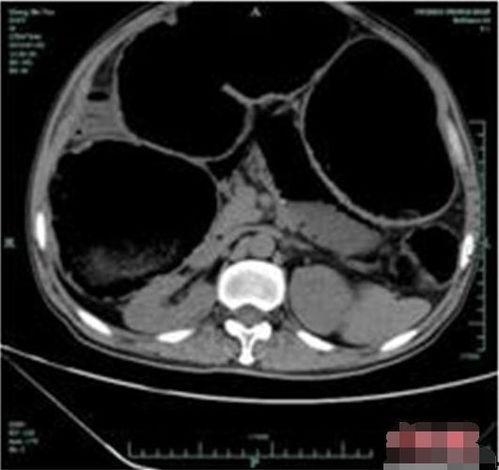

除了钡灌肠检查,CT扫描也是诊断成人巨结肠的重要手段。CT扫描可以更清晰地显示肠道的结构和功能,对于一些复杂的病例,CT扫描甚至可以替代钡灌肠检查。